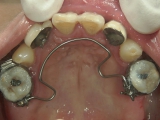

臼歯にリンガルアーチという装置を装着し、ミニインプラントを固定源に臼歯を後方に牽引します。

臼歯が後方に下がり、臼歯と小臼歯の間にスペースができました。唇側にワイヤ-をSETし、前歯の歯並びの改善を併行して行います。